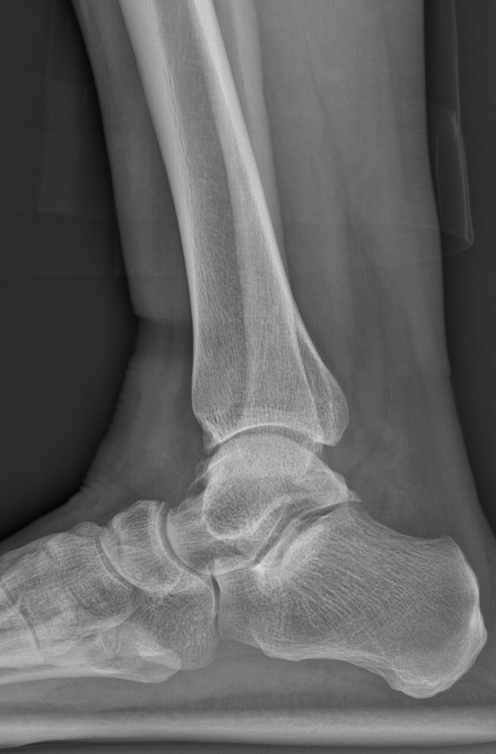

术前踝关节侧位X线

术前后足力线X线